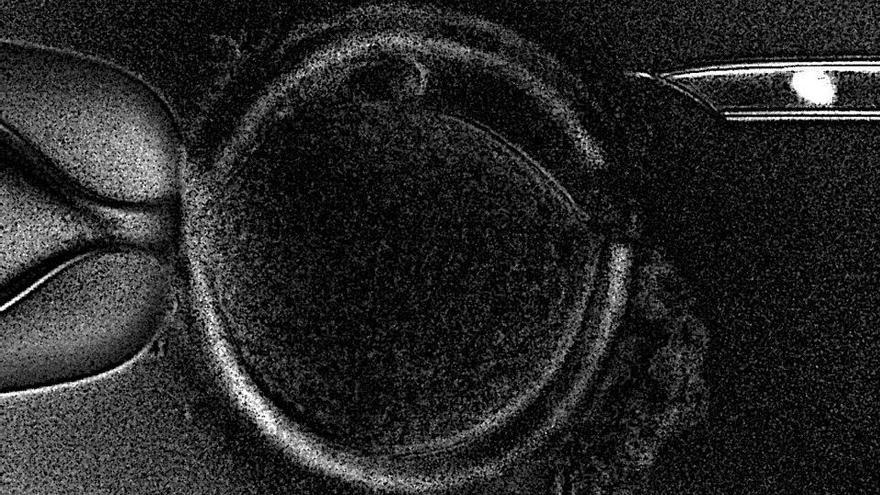

La técnica consiste en extraer el huso meiótico (núcleo) de un ovocito no fecundado de una paciente portadora de mutaciones en el ADN mitocondrial e introducirlo en el óvulo de una donante con mitocondrias sanas, del cual previamente se ha extraído su núcleo original.

Luego, el ovocito resultante es fecundado con el esperma de la pareja.